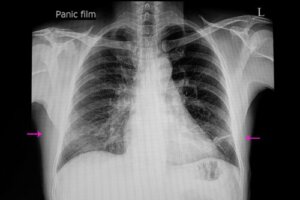

To diagnosis atelectasis, a proper clinical exploration and an X-ray will usually suffice. Just the same, doctors may use a series of techniques to confirm the diagnosis or determine the degree of seriousness.

These techniques include a CT scan (computerized tomography), bronchoscopy, ultrasound, and oximetry. In fact, bronchoscopy allows for the observation of obstructions and even the elimination of blockage.